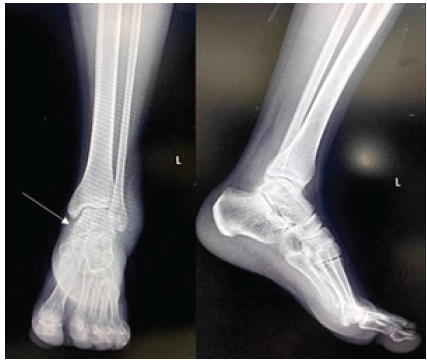

A 35-year-old male resident doctor presented with pain and swelling over the left ankle after slipping and falling on stairs. Examination revealed localized tenderness over the posteromedial aspect of the ankle with restricted movement. Plain radiographs (Fig. 1) appeared normal; however, due to high suspicion, a CT scan (Fig. 2) was performed, revealing a displaced fracture of the posteromedial process of the talus.

Figure 1: Pre-operative ankle radiographs (Anteroposterior and lateral) white arrow pointing to missed fracture.